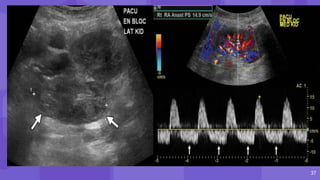

● Routine use of immediate postoperative US in the

postanesthesia care unit (PACU)

● rapid diagnosis of surgical and perioperative

complications

● renal allograft compartment syndrome (RACS)

● arteriovenous fistula (AVF)

● Pseudoaneurysm

● Hemorrhage.

• #14 Immediate postoperative power Doppler image of the left iliac fossa transplant kidney shows complete absence of cortical flow (arrows). Immediate The patient was returned to the operating room and the allograft was intraperitonealized, CASE OF compartment syndrome due to fascial compression. (b) Follow-up color Doppler image of the kidney shows good cortical flow.